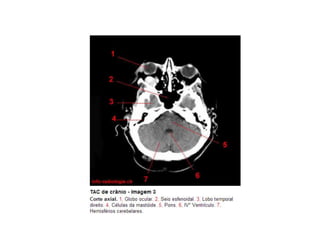

Anatomia E Protocolo Tomografia Computadorizada de Crânio PPT

Anatomia Seccional do Crâneo em Tomografia Computadorizada PPT